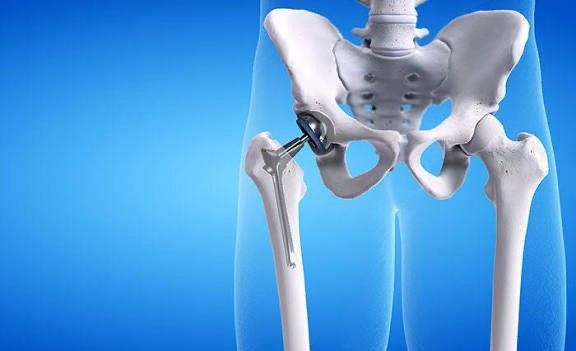

Hip Replacement — also called Total Hip Replacement (THR) or Hip Arthroplasty — is a surgical procedure where a damaged or diseased hip joint is replaced with an artificial implant made of metal, ceramic, or high-grade plastic. The goal is to relieve pain, restore mobility, and improve overall quality of life.

It’s most commonly recommended when severe arthritis, injury, or degeneration makes daily activities like walking, climbing stairs, or even sitting painful and difficult.

Hip replacement is advised when non-surgical treatments like medications, physiotherapy, or injections no longer provide relief.

Osteoarthritis – Wear-and-tear arthritis causing cartilage loss

Rheumatoid Arthritis – Inflammatory arthritis damaging the joint

Avascular Necrosis – Bone collapse due to poor blood flow

Post-Traumatic Arthritis – Arthritis after hip injury or fractures

Hip Dysplasia – Abnormal hip development leading to degeneration